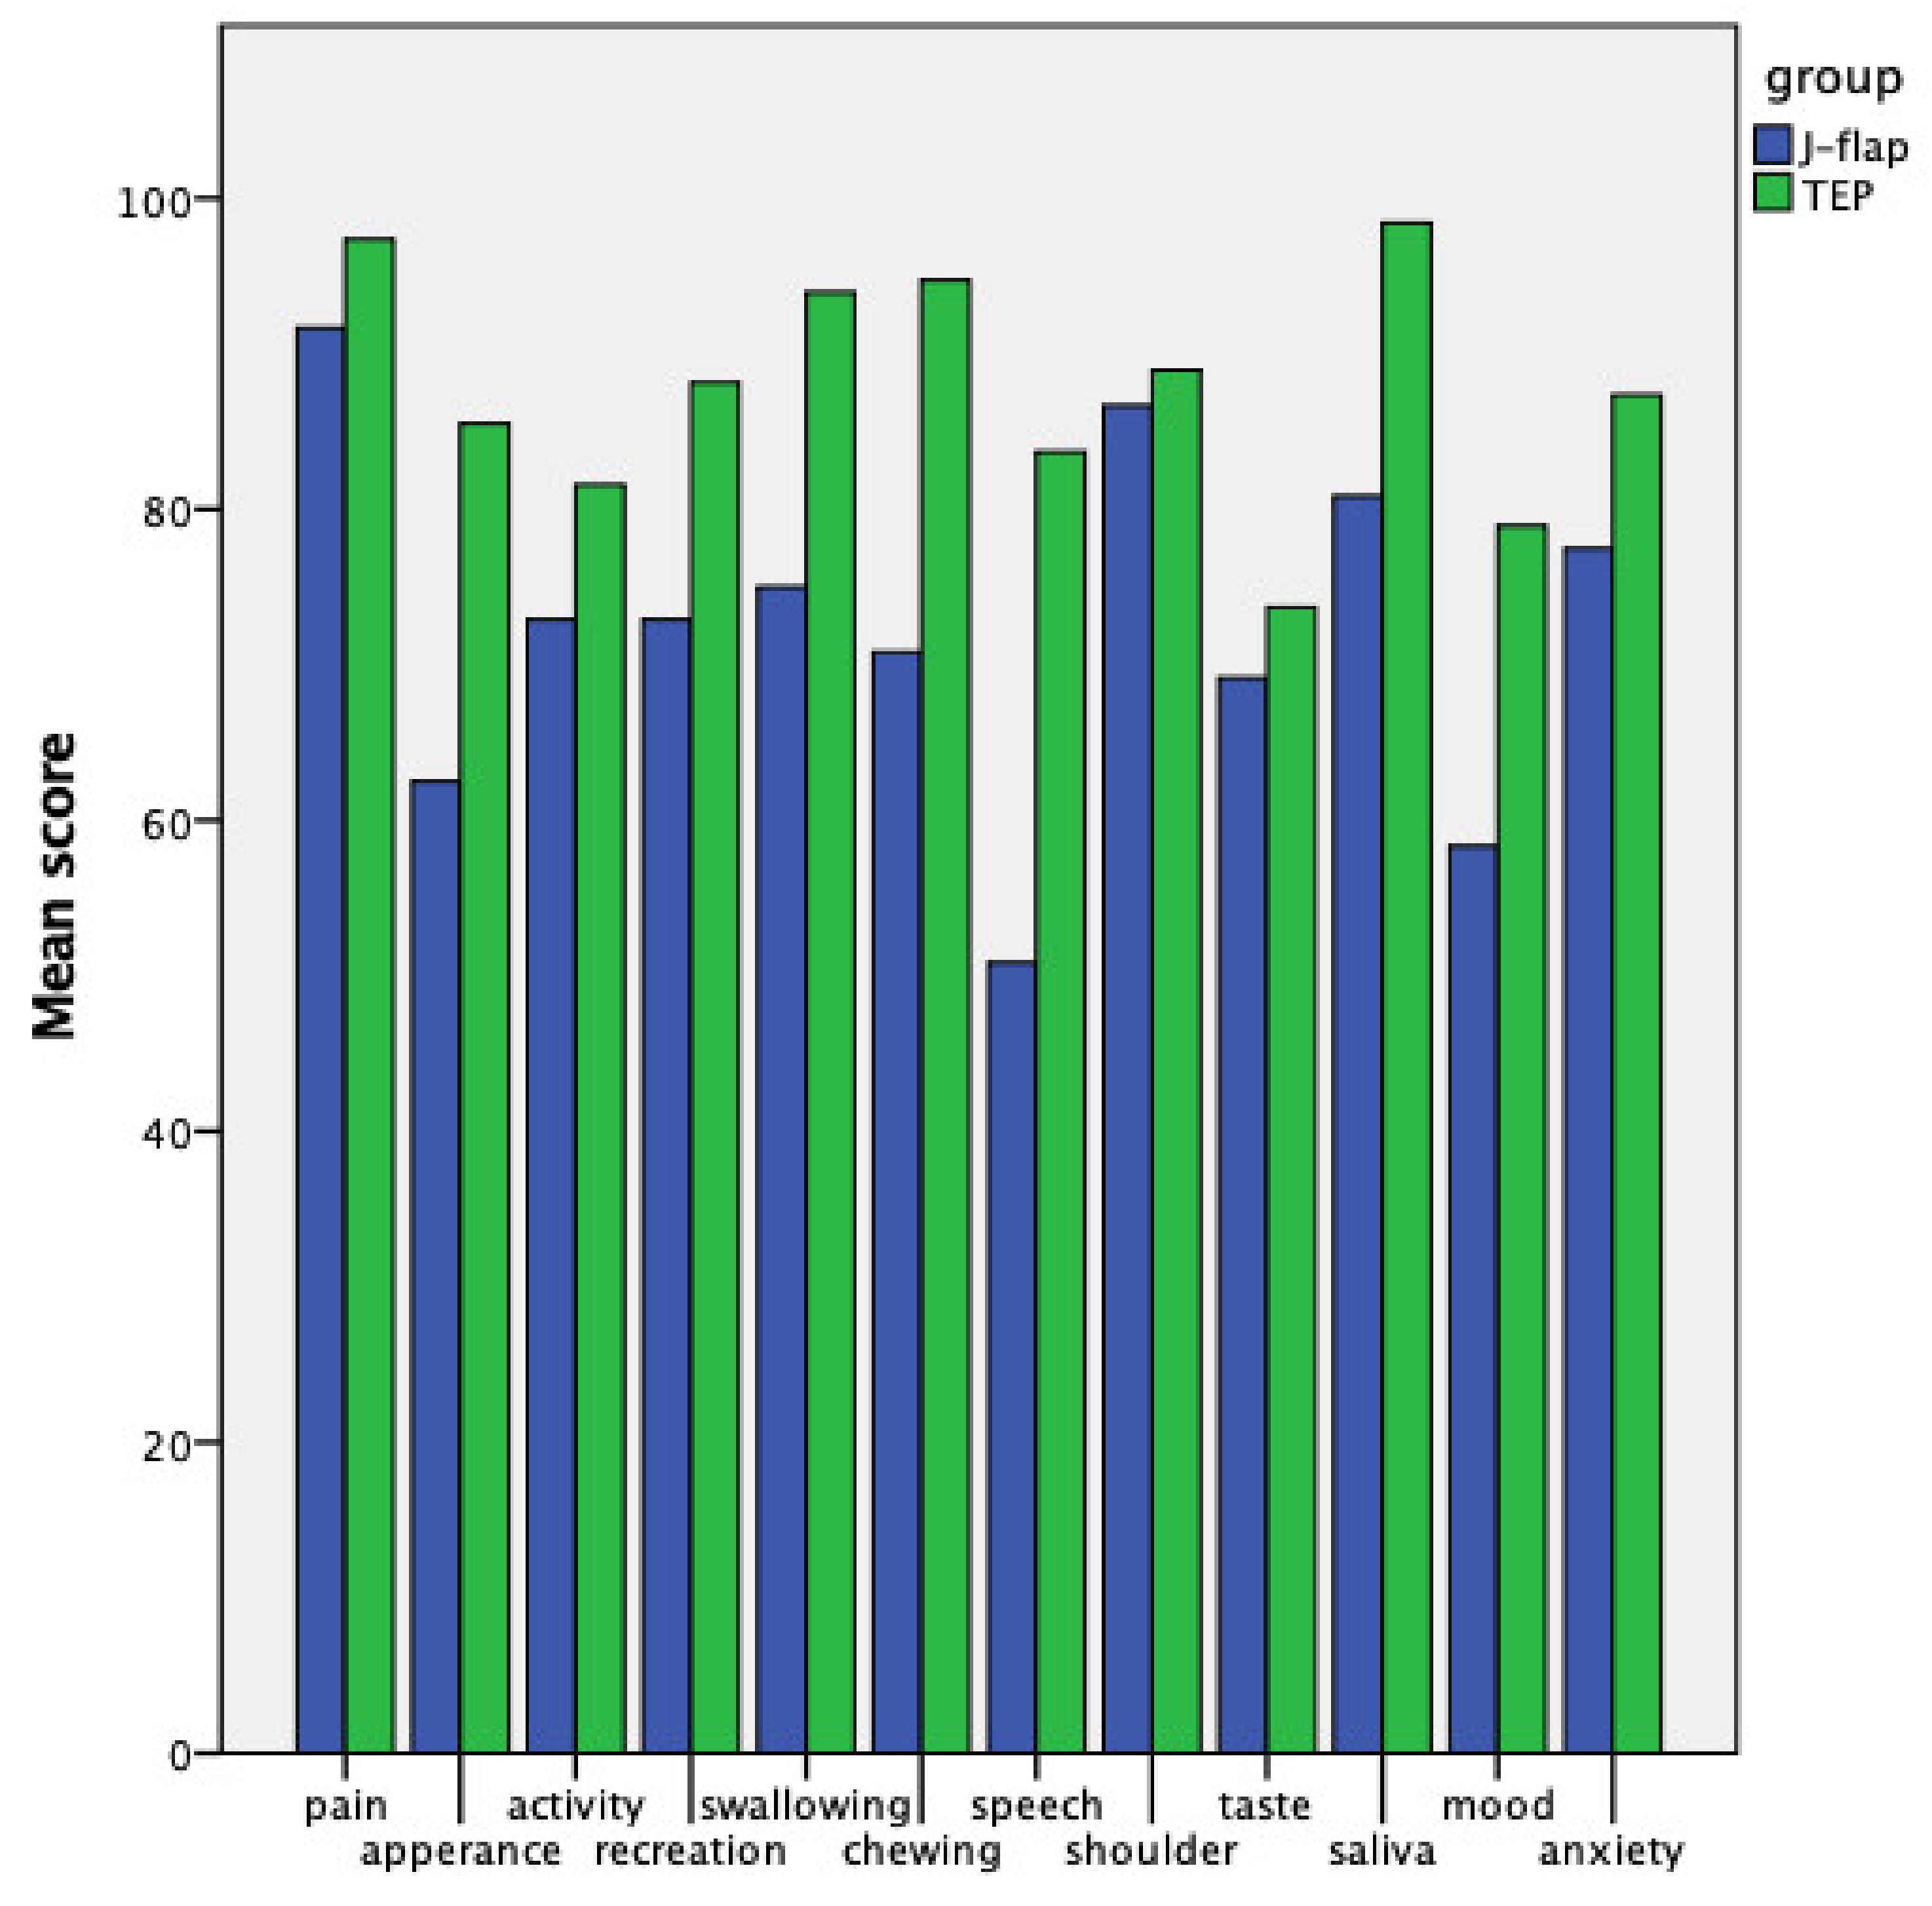

| University of Washington Quality of Life (QoL) Questionnaire | J-Flap Group | TEP Group | p-Value |

| Physical function subdomain | 68.19 ± 21.65 | 88.33 ± 9.46 | 0.009 |

| Social-emotional function subdomain | 76.67 ± 19.14 | 87.06 ± 7.65 | 0.09 |

| QoL composite | 72.43 ± 18.30 | 87.69 ± 6.42 | 0.016 |